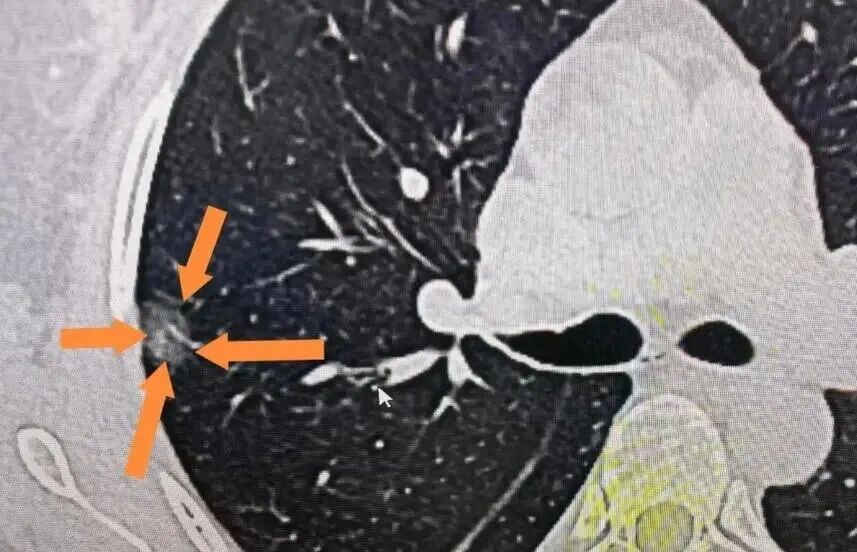

体检发现肺结节,很多人一夜难眠。其实,看懂影像中的形态、大小变化和个人背景,就能判断危险信号。抓住观察期,用好中医调理与随访,多数...[详情]

TAG标签:理性看结节 早期干预